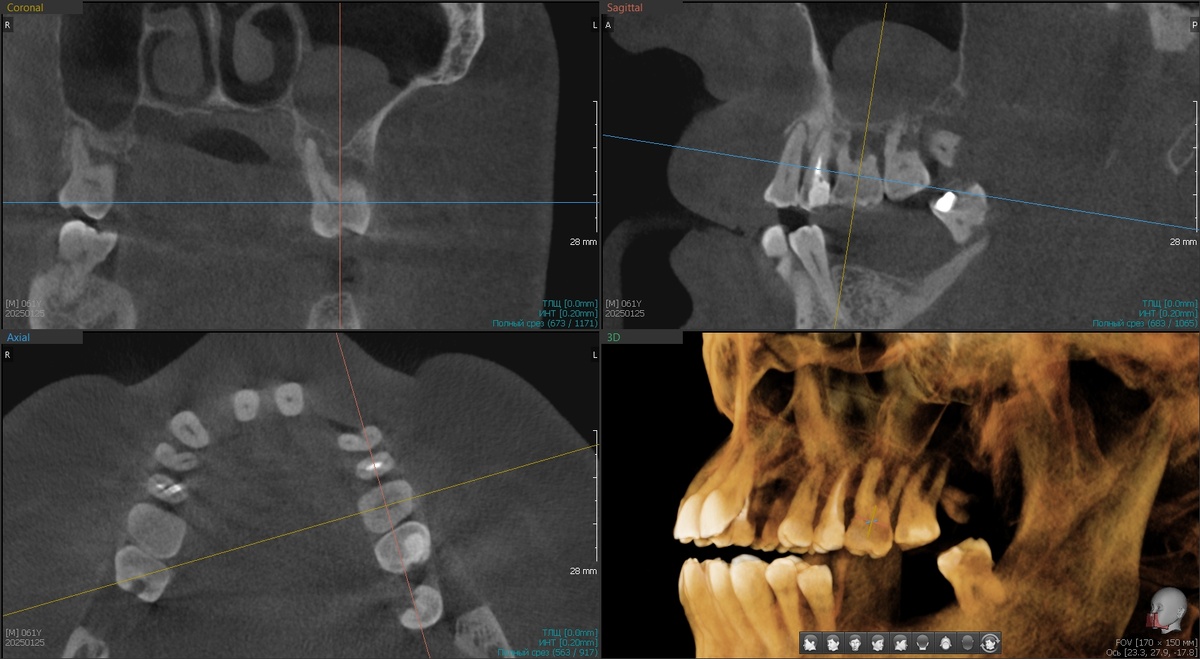

Имплантаты в кости (на штыри "пины" не обращайте внимания, снимок делался в процессе имплантации, что бы оценить постановку и что-то куда-то докрутить при необходимости).

Тут что хочу добавить важное - работа будет не на 4 имплантатах, а на 6, когда приживутся те "болты", что поставили в этот раз, добявят ещё по одному птеригоидному с 2х сторон. Сейчас же даже не все зубы удалили на верхней челюсти, что-то из жевательных осталось для фиксации прикуса (временно).